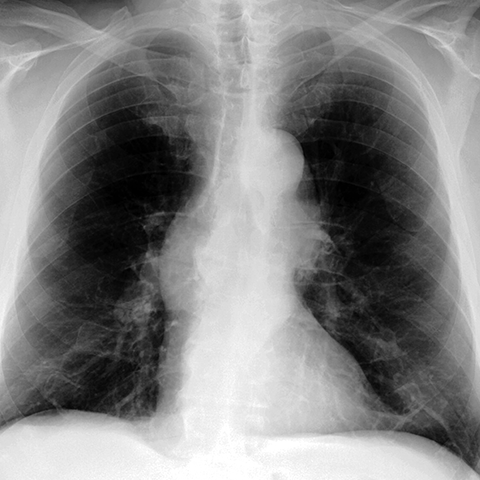

Aortic Enlargement and Tortuosity [1 of 2]